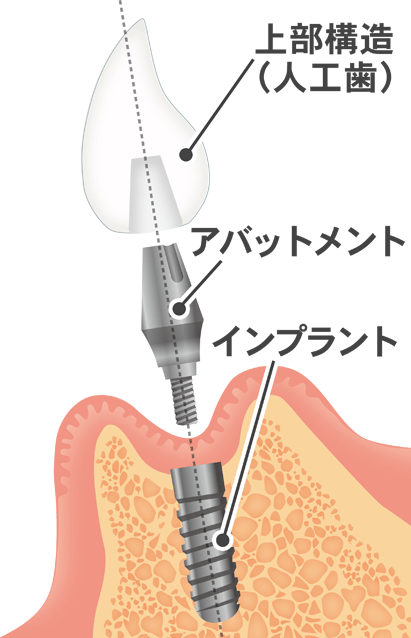

⑥ 前回詰めた綿花の状態を確認して、良い状態なら、「根管充填剤」(マスターポイント・アクセサリーポイント)というお薬を、余分な空間がないように根っこに詰めます。

⑥ 前回詰めた綿花の状態を確認して、良い状態なら、「根管充填剤」(マスターポイント・アクセサリーポイント)というお薬を、余分な空間がないように根っこに詰めます。 Q1.痛みはありますか?

Q1.痛みはありますか? ② 次に、「根管長測定器」という機械を使い、根っこの長さを正確に測ります。

② 次に、「根管長測定器」という機械を使い、根っこの長さを正確に測ります。

⑤ 次に、仮詰めをします。

⑤ 次に、仮詰めをします。 虫歯が神経まで達して炎症を起こしているので、人によってはズキズキとした痛みを感じる方もいます(>_<)

虫歯が神経まで達して炎症を起こしているので、人によってはズキズキとした痛みを感じる方もいます(>_<)